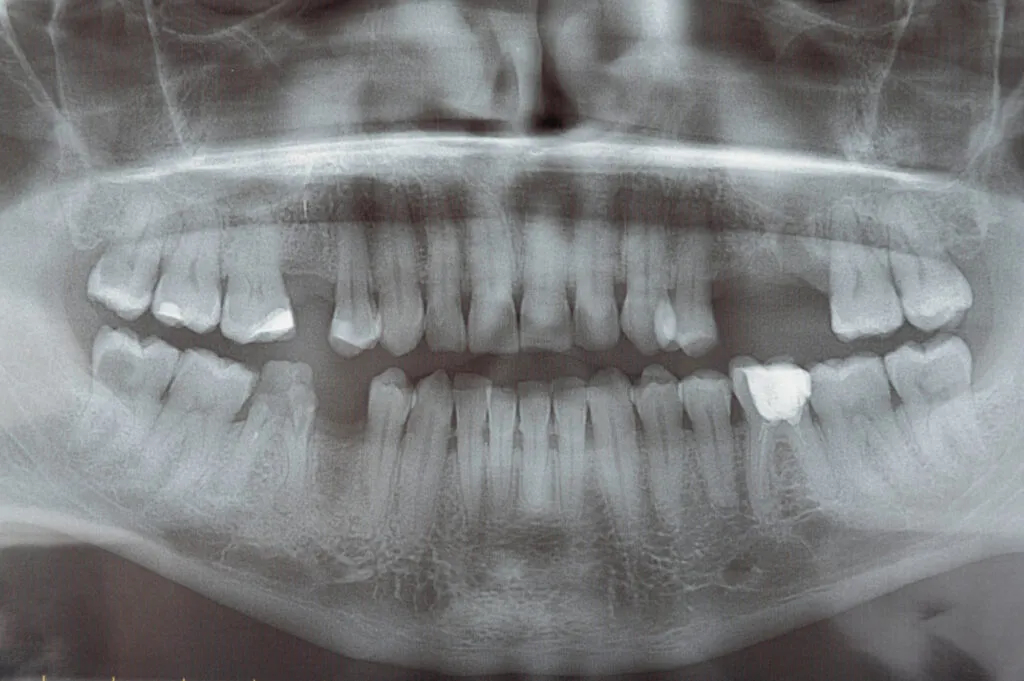

1. Panoramic X-ray

A panoramic X-ray reveals the whole mouth area. This type of X-ray identifies impacted teeth, shows your wisdom teeth’ progression, and helps diagnose tumors.